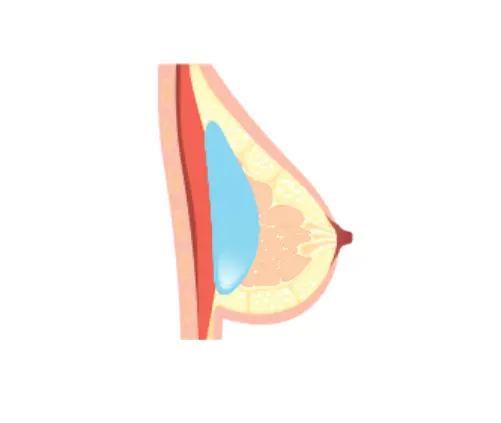

Implant Placement Options

| Placement | Above Muscle | Under Muscle | Dual Plane (Partial Submuscular) |

|---|---|---|---|

| Advantages | – Suitable for sagging or deflated breasts – Natural shape – Less pain and simpler surgery | – Suitable for smaller breasts – Can prevent capsular contracture – More natural result | – For patients with thin skin or low body fat – Reduces implant visibility – Prevents infection – Keeps implant securely in place |

| Disadvantages | – May look unnatural if patient has little fat – Higher risk of capsular contracture | – Slight pain due to tension between muscle and implant – Slightly longer recovery time | – Difficult to position implant if muscles are thick – Risk of muscle tearing or asymmetry |

Above Muscle

Under Muscle

Dual Plane (Partial Submuscular)